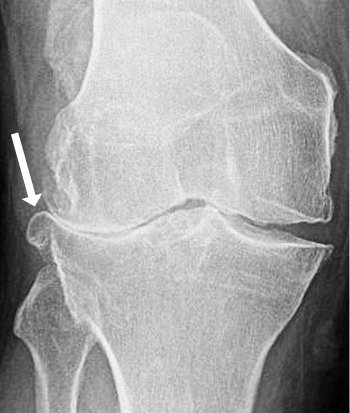

X-ray image of bone spur in an osteoarthritic knee. Note the closure of the joint space on that side, implying destruction of the joint cartilage and/or meniscus.

Bone spurs occur in response to joint surface damage, where the body tries ineffectually to heal the damage by absorbing bone from some areas, leaving holes or cysts, and then heaping it up in other areas, making bone spurs or osteophytes.

Small spurs are seldom a problem - rather they are just an X-ray indicator that there is an arthritic process going on inside the knee. But if the bone spurs do become large and symptomatic, they can be abraded away using a rotating burr (by arthroscopic abrasion or abrasion arthroplasty).